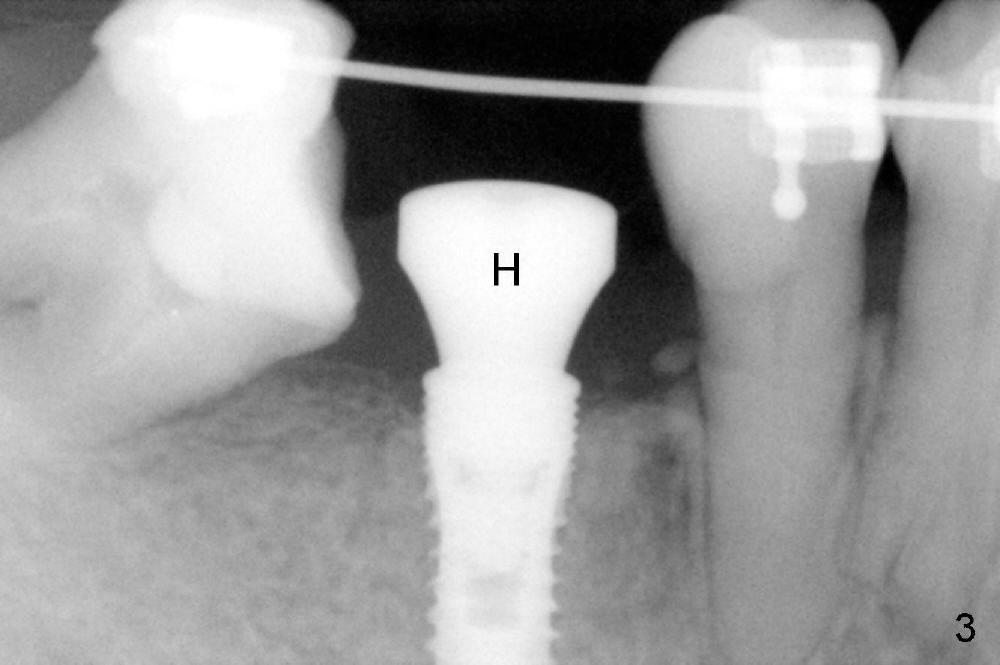

Four months later, the implant appears to have osteointegrated (Fig.3; H: healing abutment).

An abutment is placed; a provisional is fabricated, a premolar band is tried in and cemented (Fig.4: #30). Next visit, the implant will be used as an anchorage to distalize #29 and 28 (arrow) so that there is enough space to restore the distal defect of #27 (*).